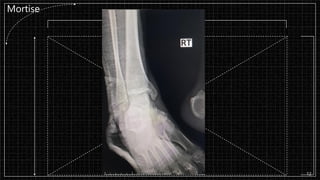

Mortise

▪ Film : Rt. Ankle AP, LAT, Mortise

LAT